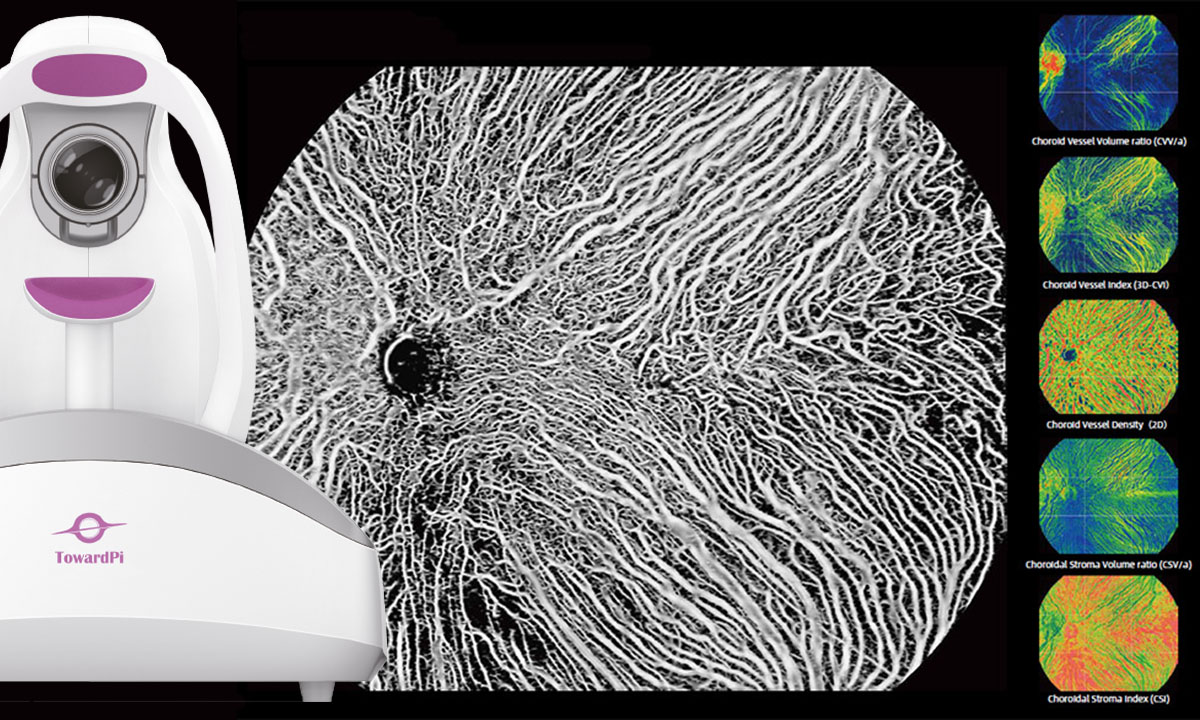

19.02.2026 | bon Optic Vertriebsges. mbH gesponsert 400.000 A-Scans pro Sekunde – Ist das zu schnell für Sie? Das Ultra-High-End OCT von TowardPi setzt neue Maßstäbe mit einer beeindruckenden Scangeschwindigkeit von 400 kHz, 3,8 μm Auflösung und einem 24×20 mm Weitwinkel-OCTA. Weiterlesen 1009